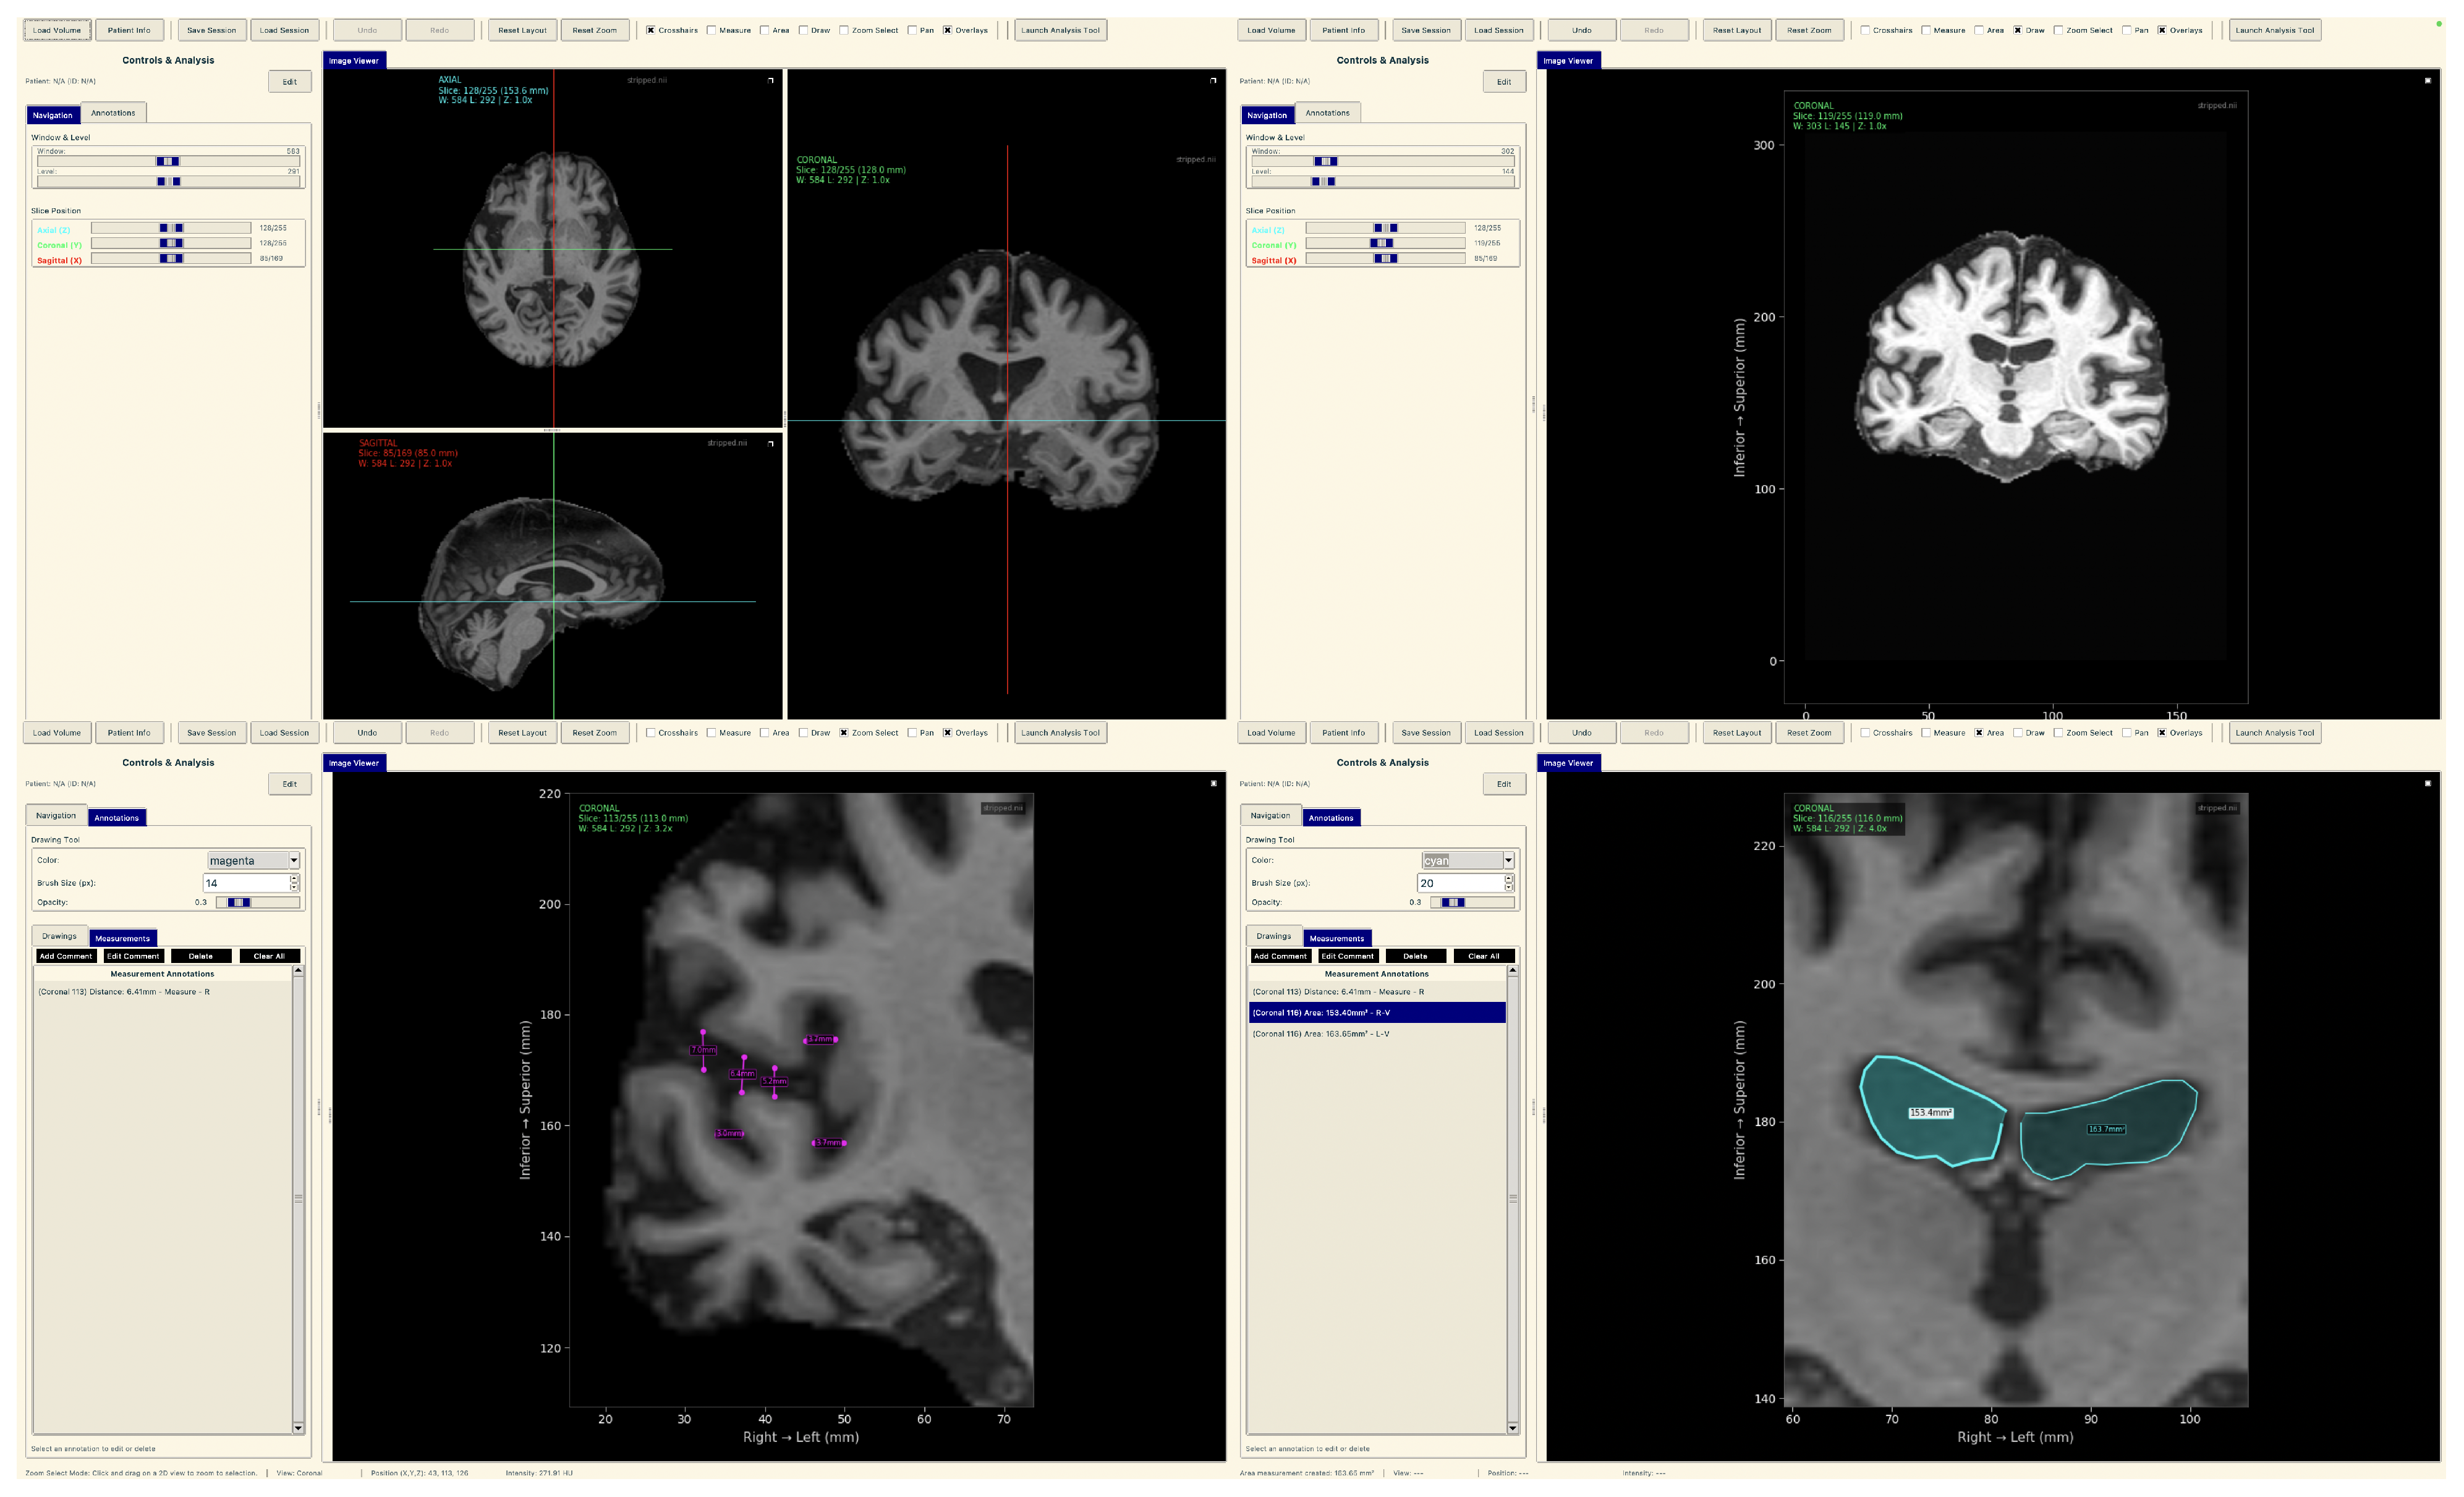

Neuroimaging Analysis Tool

To demonstrate practical deployment of our lightweight explainable framework, we developed a neuroimaging analysis application that integrates our trained models with real-time explainability visualization for clinical evaluation workflows.

The tool consists of two main components: a comprehensive slice viewer for medical image navigation and annotation, and a specialized XAI analysis module for model inference and explainability visualization. The slice viewer implements medical imaging functionality including multi-planar viewing, window/level adjustment, measurement capabilities, and annotation tools using Python 3.11.3 with SimpleITK 2.5.2 for medical image handling and TensorFlow for neural network execution. The analysis module integrates our best model, the EfficientNetV2B0 model trained on augmented data with configurable layer selection for different explainability methods. The system includes dynamic layer configuration interfaces that automatically detect convolutional layers in loaded models and enable users to specify attribution layers for Grad-CAM++, Guided Grad-CAM++, and consensus attribution maps across different architectures.

The tool consists of two main components: a comprehensive slice viewer for medical image navigation and annotation (Figure 30), and a specialized XAI analysis module for model inference and explainability visualization (Figure 31). The slice viewer implements medical imaging functionality including multi-planar viewing, window/level adjustment, measurement capabilities, and annotation tools using Python with SimpleITK for medical image handling and TensorFlow for neural network execution.

Figure 30.

Neuroimaging slice viewer interface demonstrating MRI visualization capabilities.

Figure 31.

Analysis tool interface demonstrating AI explainability features.

The analysis tool implements a simplified preprocessing pipeline suitable for demonstration purposes, including basic cropping and resizing to the required input dimensions . The complete preprocessing pipeline described in the data set and preprocessing (Section 3.1) should be applied before using this tool.

The application maintains computational efficiency suitable for standard clinical hardware while providing session management, annotation capabilities, and structured reporting. The modular architecture supports both clinical demonstration and research validation, enabling comparative studies of lightweight architectures within a consistent framework. The complete implementation serves as a proof-of-concept for the deployment of accessible AI tools in routine clinical settings.